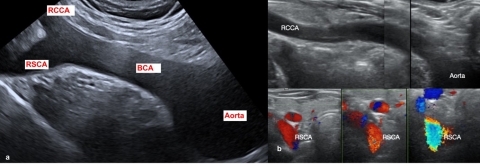

Figure 2 : Exploration échographie de la division du tronc brachiocéphalique.

a)  Image en Y reflétant la division normale du tronc brachiocéphalique (BCA). La sonde est positionnée transversalement à l’orifice cervico-médiastinale. Après identification de la carotide commune droite (RCCA), la sonde est orientée de manière caudale cherchant la division du tronc brachiocéphalique.

b) Absence de l’image en Y avec une carotide commune droite (RCCA) émergeant directement de l’arc aortique, et une artère sous-clavière droite présentant un flux antéro-postérieur.